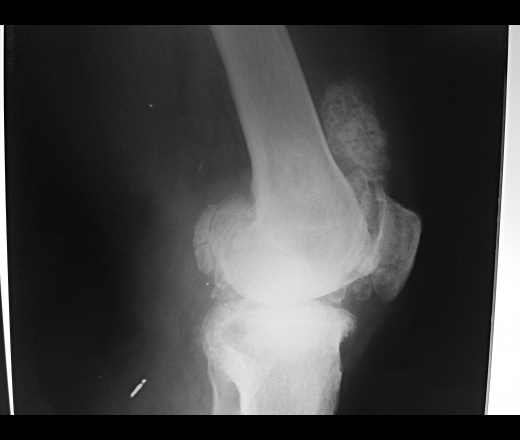

Медицинские аспекты заболеваний: рентгенологическая картина туберкулеза костей

Раздел: Снимки-откровения